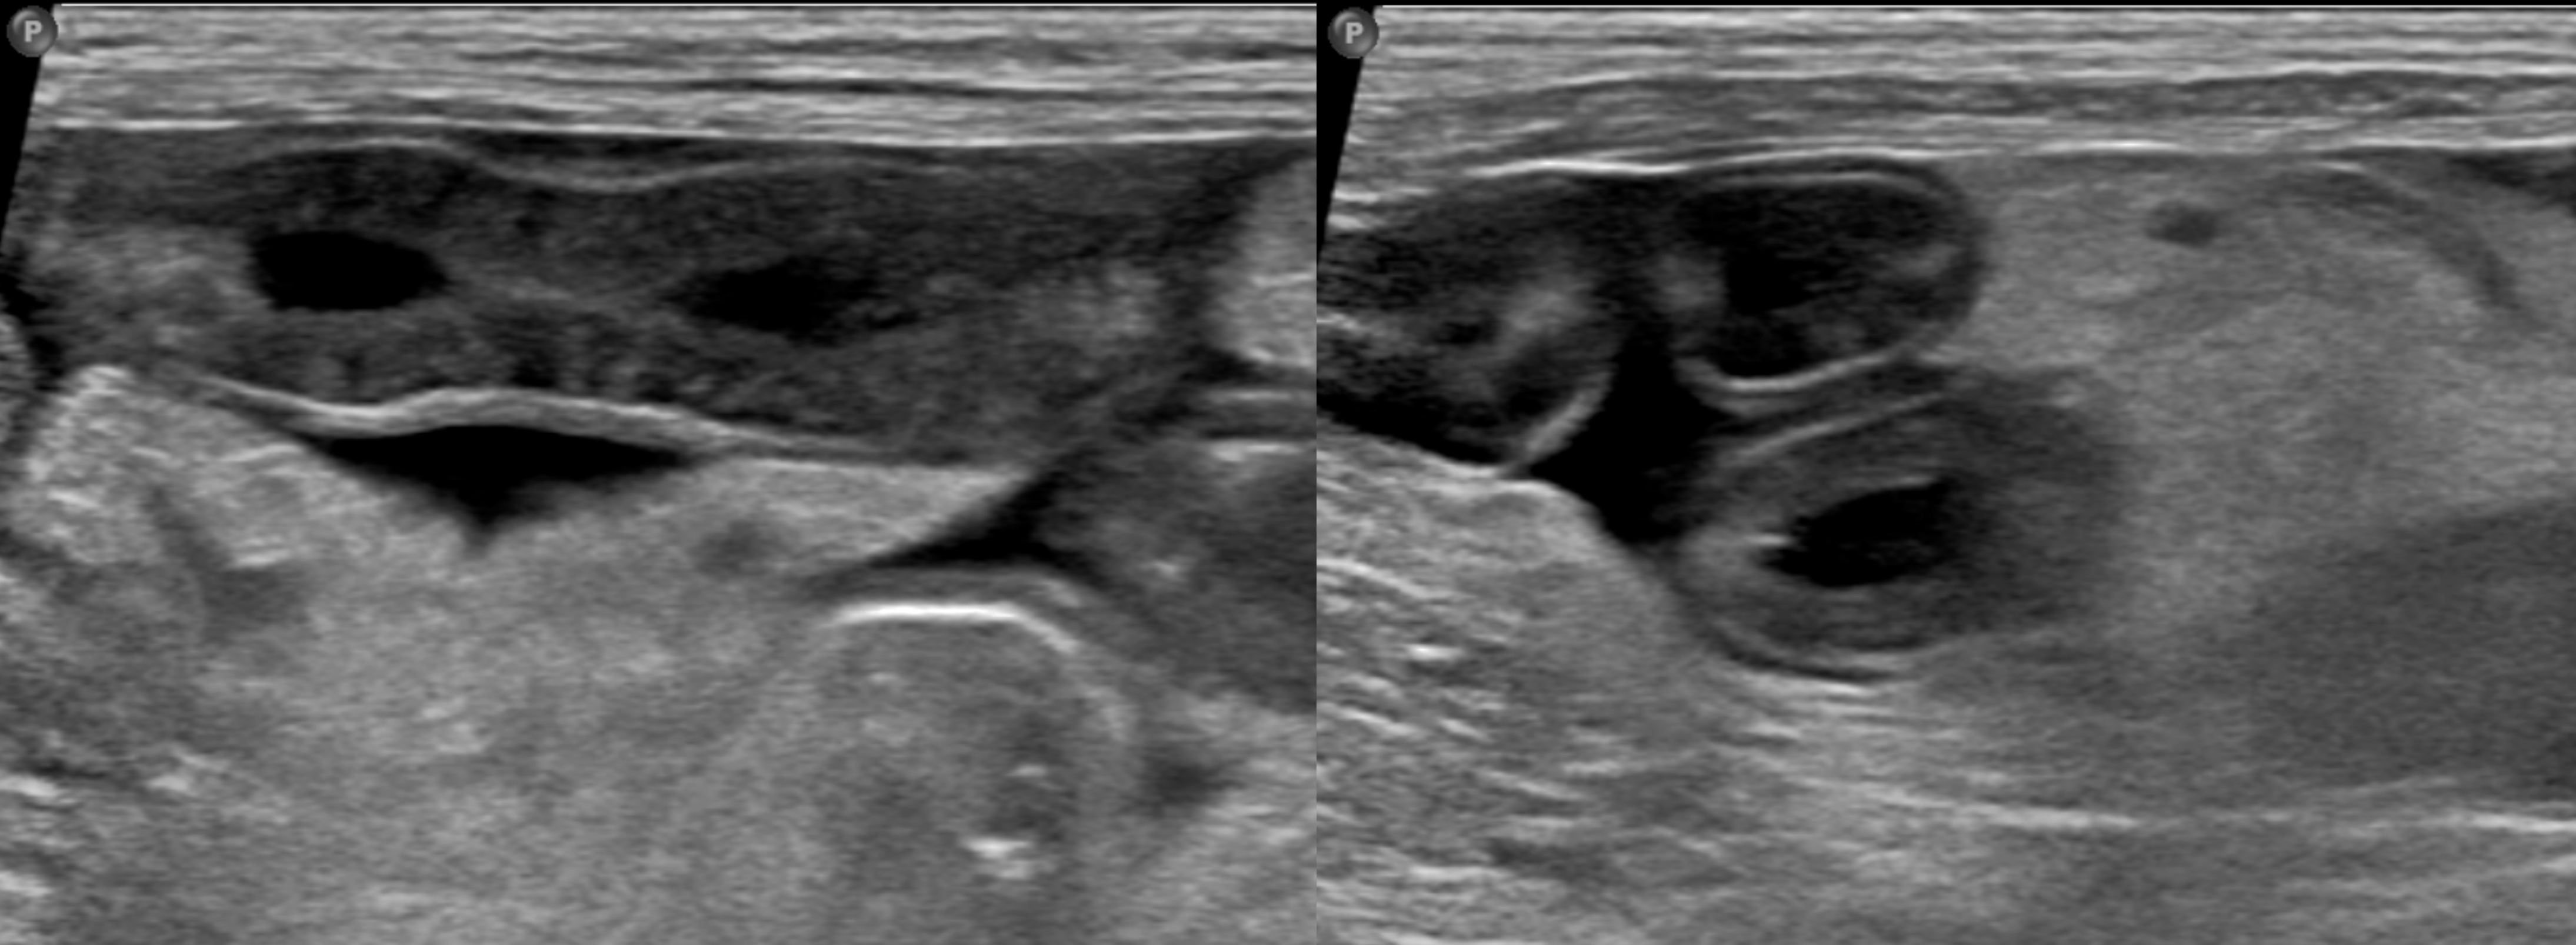

(초음파 검사)

초음파 검사 결과  복수 및 장간막 부종성 변화와 더불어 공장 분절 광범위한 부위에서 lymphangiectasis 의심 소견이 확인되었다.